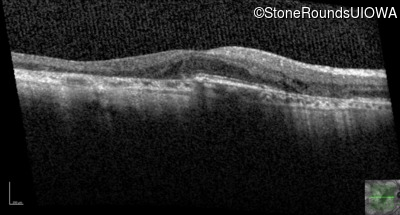

Age at visit: 54 years

Age at visit: 54 years (Visit 2)